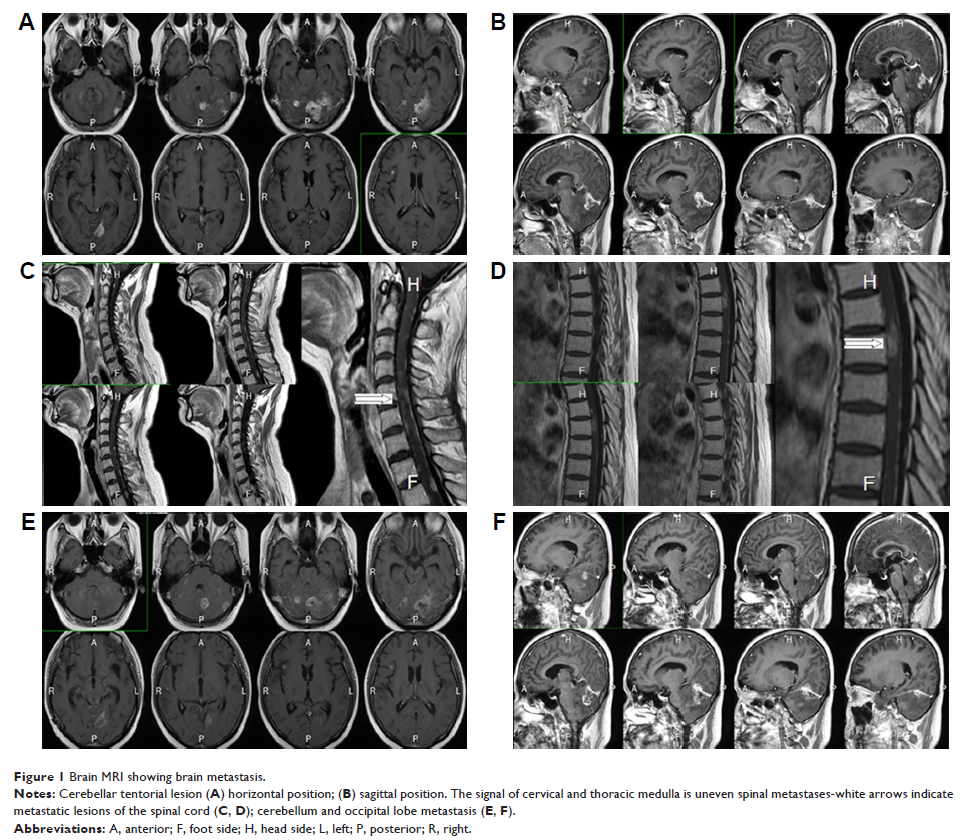

Case Report

- 作者:Yushan Han, Xia Zhang, Yishan Lu, Yan Dong, Hong Fu, Bin Zhang, Yajie Gao

- 期刊:OncoTargets and Therapy